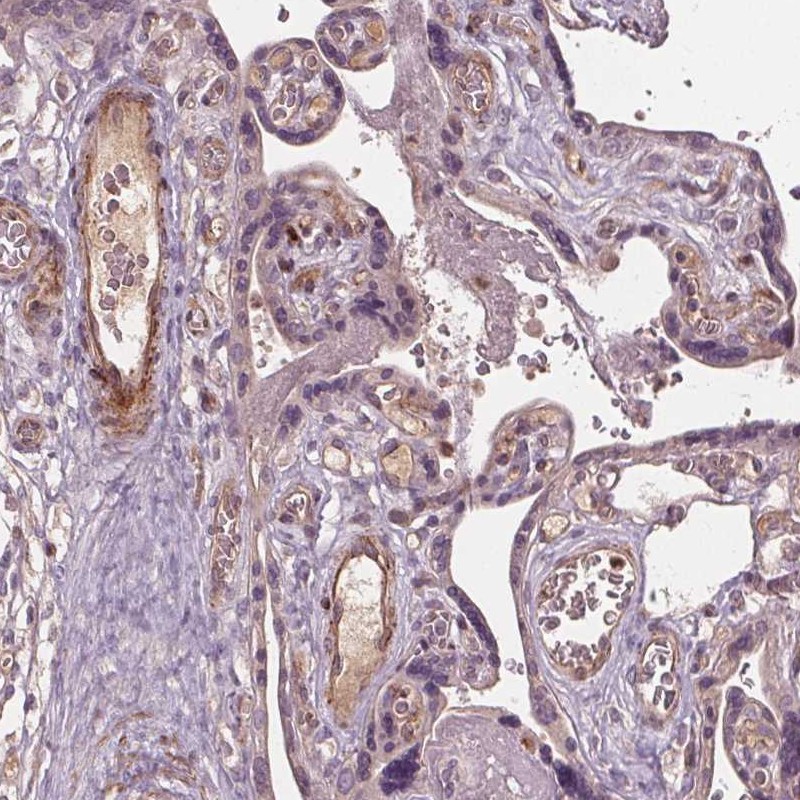

Immunohistochemical staining of human placenta shows moderate cytoplasmic positivity in wall of blood vessels.